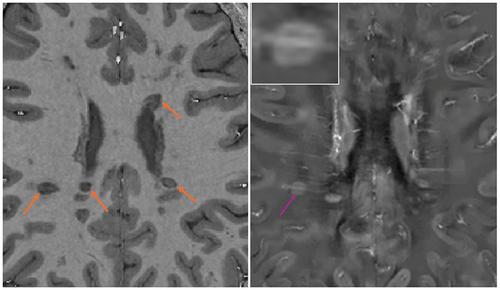

Chronic active multiple sclerosis (MS) lesions represent a particularly destructive subset of lesions on pathology. However, their imaging correlates, including paramagnetic rim lesions (PRLs) detected on susceptibility-weighted imaging, lack sensitivity and are difficult to implement in clinical practice. This exploratory, longitudinal study investigates the prevalence and temporal dynamics of a novel imaging marker, T1-dark rims, and their relationship with PRLs observed on quantitative susceptibility mapping (QSM).

Four untreated people with MS underwent 7-Tesla MRI scanning six times over a period of 36 weeks. New and pre-existing lesions were analyzed for the presence and temporal evolution of T1-dark and QSM rims. Quantitative T1 values were derived using B1 maps, and the relationship between rim status and lesion size was evaluated.

Of the 159 baseline lesions, 22 (14%) had T1-dark rims, 11 (7%) had QSM rims, and five lesions had both. T1-dark and QSM rims showed temporal changes, with T1-dark rims preceding new QSM rim appearance in three out of four (75%) lesions. Eleven out of 20 (55%) newly formed lesions had T1-dark rims, with a T1-dark rim present in all new lesions over 100 mm3. Small new lesions lacked discernible rims, but their overall T1 values aligned with those of larger lesion T1-dark rims implying shared pathological processes.

T1-dark rims were more common than QSM rims, with greater prevalence in newly formed lesions. We propose they represent edema and inflammation associated with early stages of chronic active lesion formation visible despite, not because of, iron accumulation.